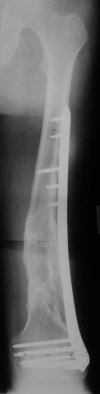

Synthes 4.5 mm LCP (Locking Condylar Plate) is slightly different, more anatomical shape and larger (wider) than original LISS. I personally use it when I have more difficult, Type C fractures where larger incision is necessary in order to reconstruct the joint.

For cases with less comminution and those that require longer plates (more involvement of distal third of femur), I rather go with LISS because is

possible to put the screws truly percutaneously (stab incisions, outside guide). Both systems are available and in use... :) .